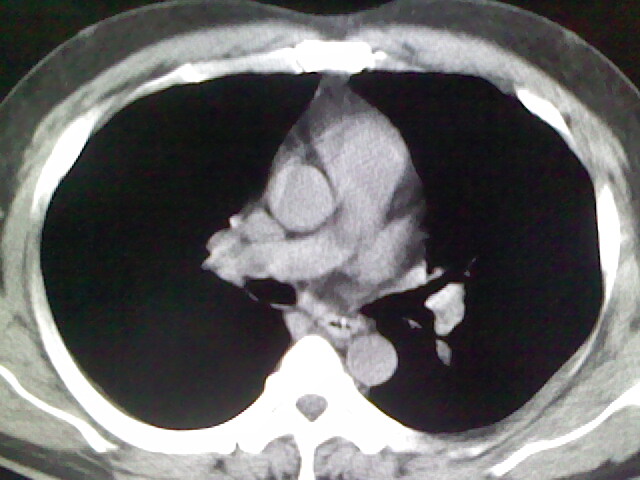

标题: CT17932:临床怀疑肺栓塞

男,34岁,自觉右侧胸痹,胸闷3天余

右侧肺动脉似见密度稍低影,请在机器的薄层上再看看有没有充盈缺损。